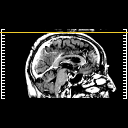

Glioma overlay -- Slice #119

[Home][Help][Clinical] Slice 119